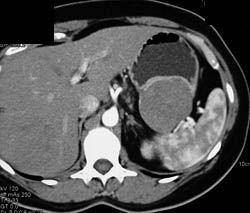

Diagnosis

Antral Carcinoma